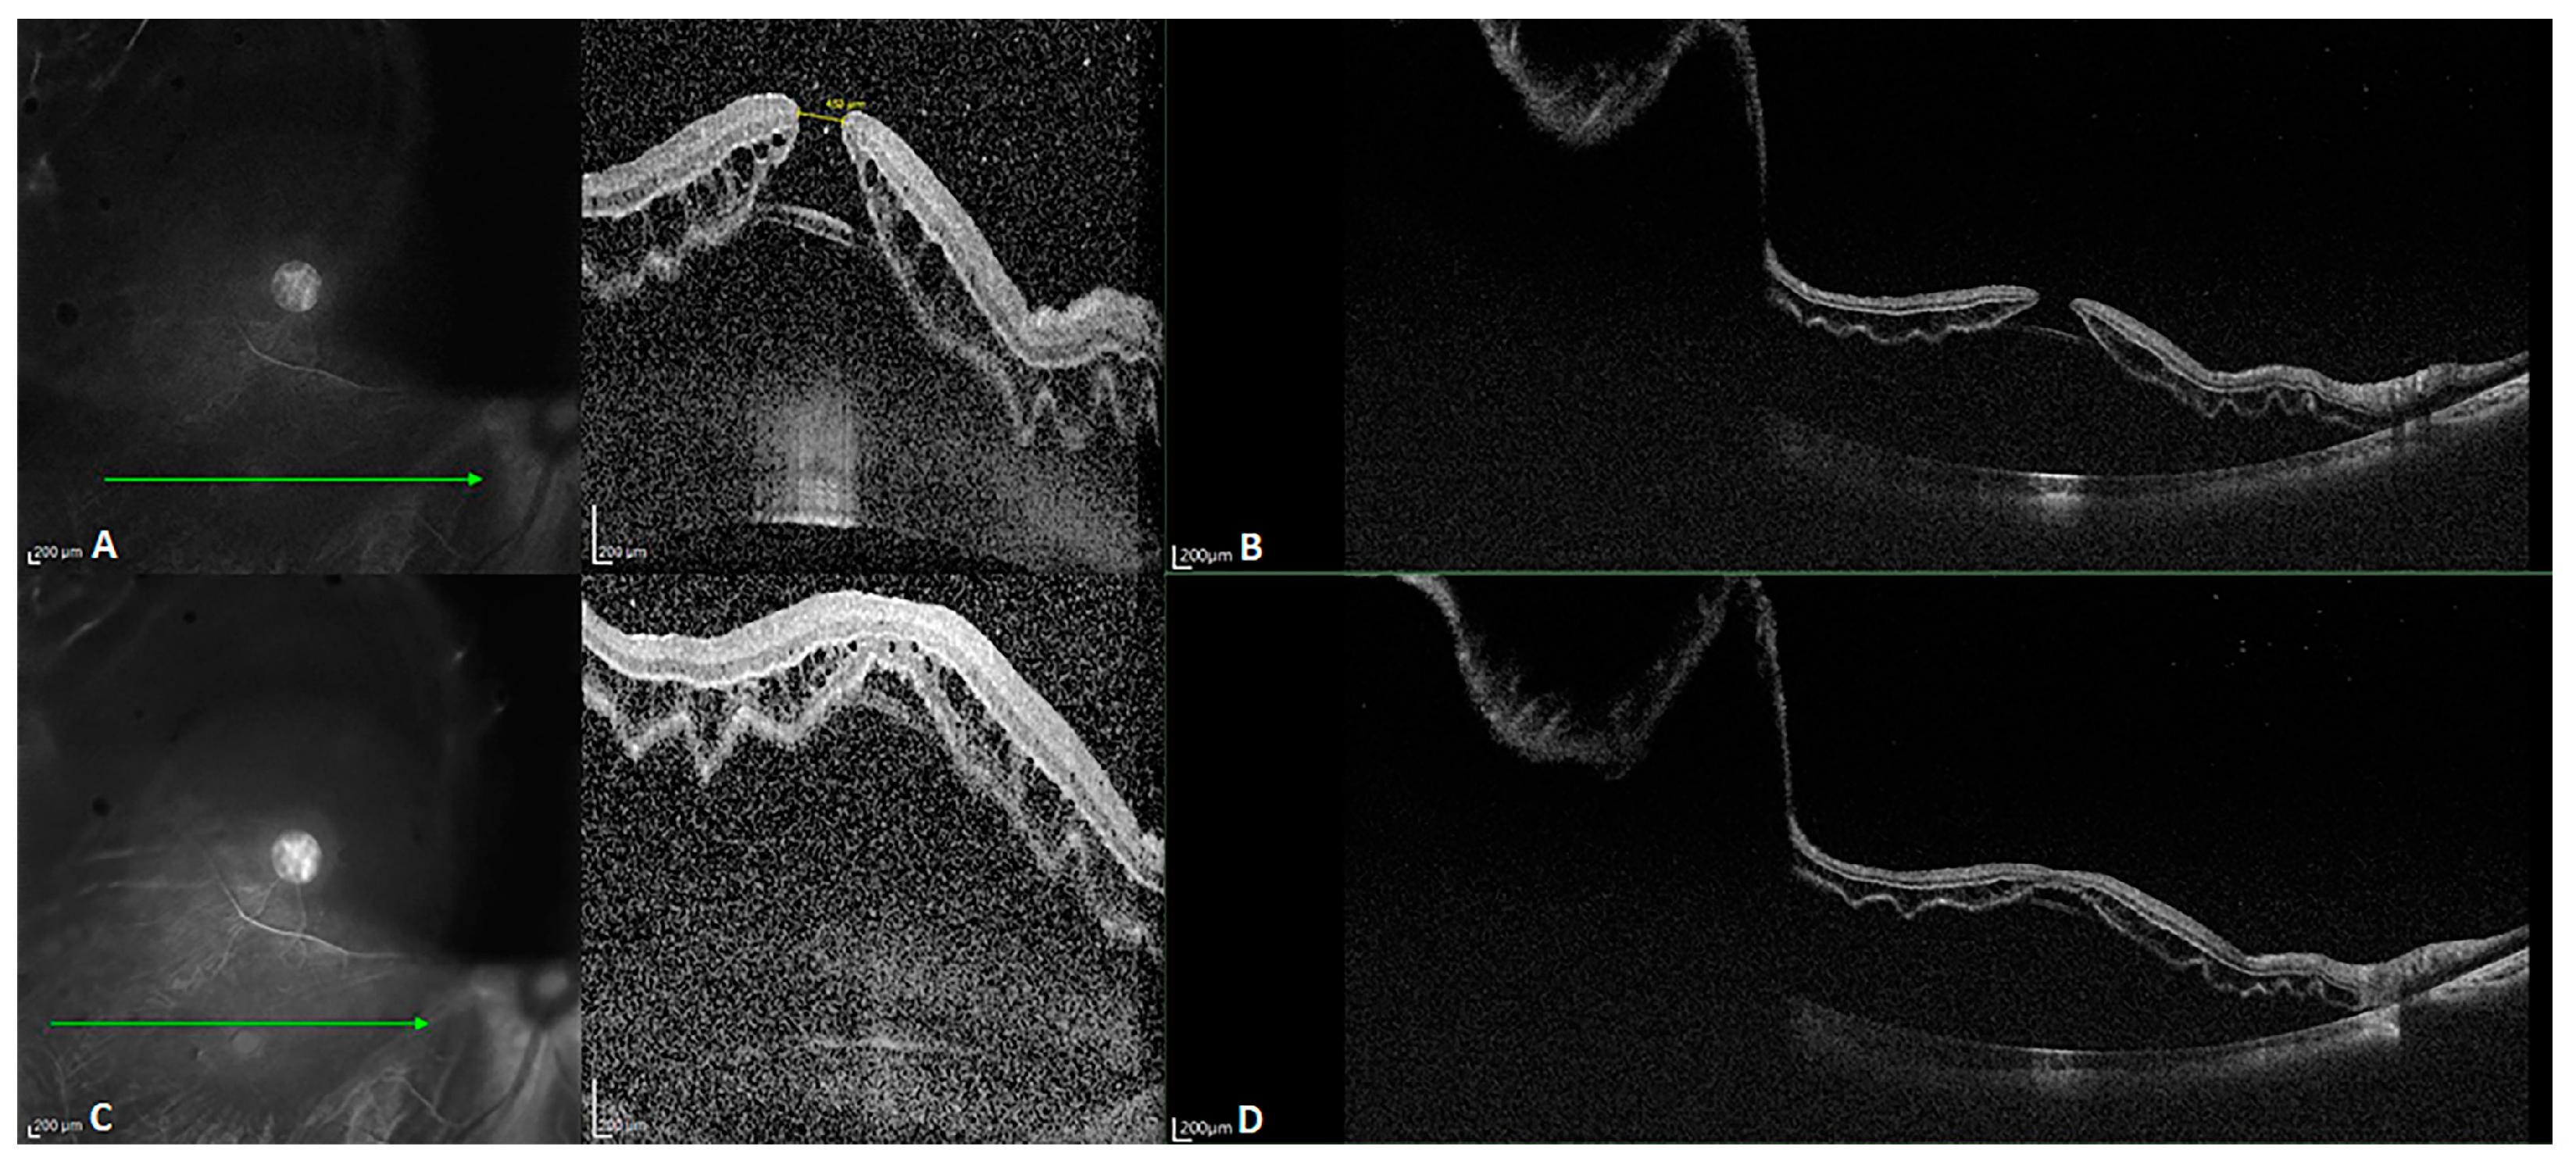

facile structure, which efficiently restrains common mode noise. As a consequence, even at the same scanning speed, SS-OCT yields a better sensitivity and higher image signal-to-noise ratio (SNR) than SD-OCT, even in the case of weak OCT signals due to refractive medium turbidity, such as that caused by cataracts or vitreous hemorrhage. This latter shortcoming is overcome by the penetration depth and sensitivity of the technique. Figure 2 reveals the difference between SD- and SS-OCT in acquiring retinal images from a patient with refractive medium turbidity. SS-OCT is better able to display the characteristics of tissue structures, improving clinical diagnosis.

Figure 2.

B-scan images of a patient with refractive medium turbidity and a huge choroidal coloboma. (A) Spectral-domain OCT (SD-OCT) image showing a part of the coloboma, but the structure is blurry (The green arrow in the left image indicated the orientation of B scan OCT in the right image). (B) An oblique SS-OCT scan of the same choroidal coloboma and the macular area. Even the posterior scleral space can be visualized. (C) A B-scan SS-OCT image with a range of 20 × 20 mm showing the full extent of the choroidal coloboma.